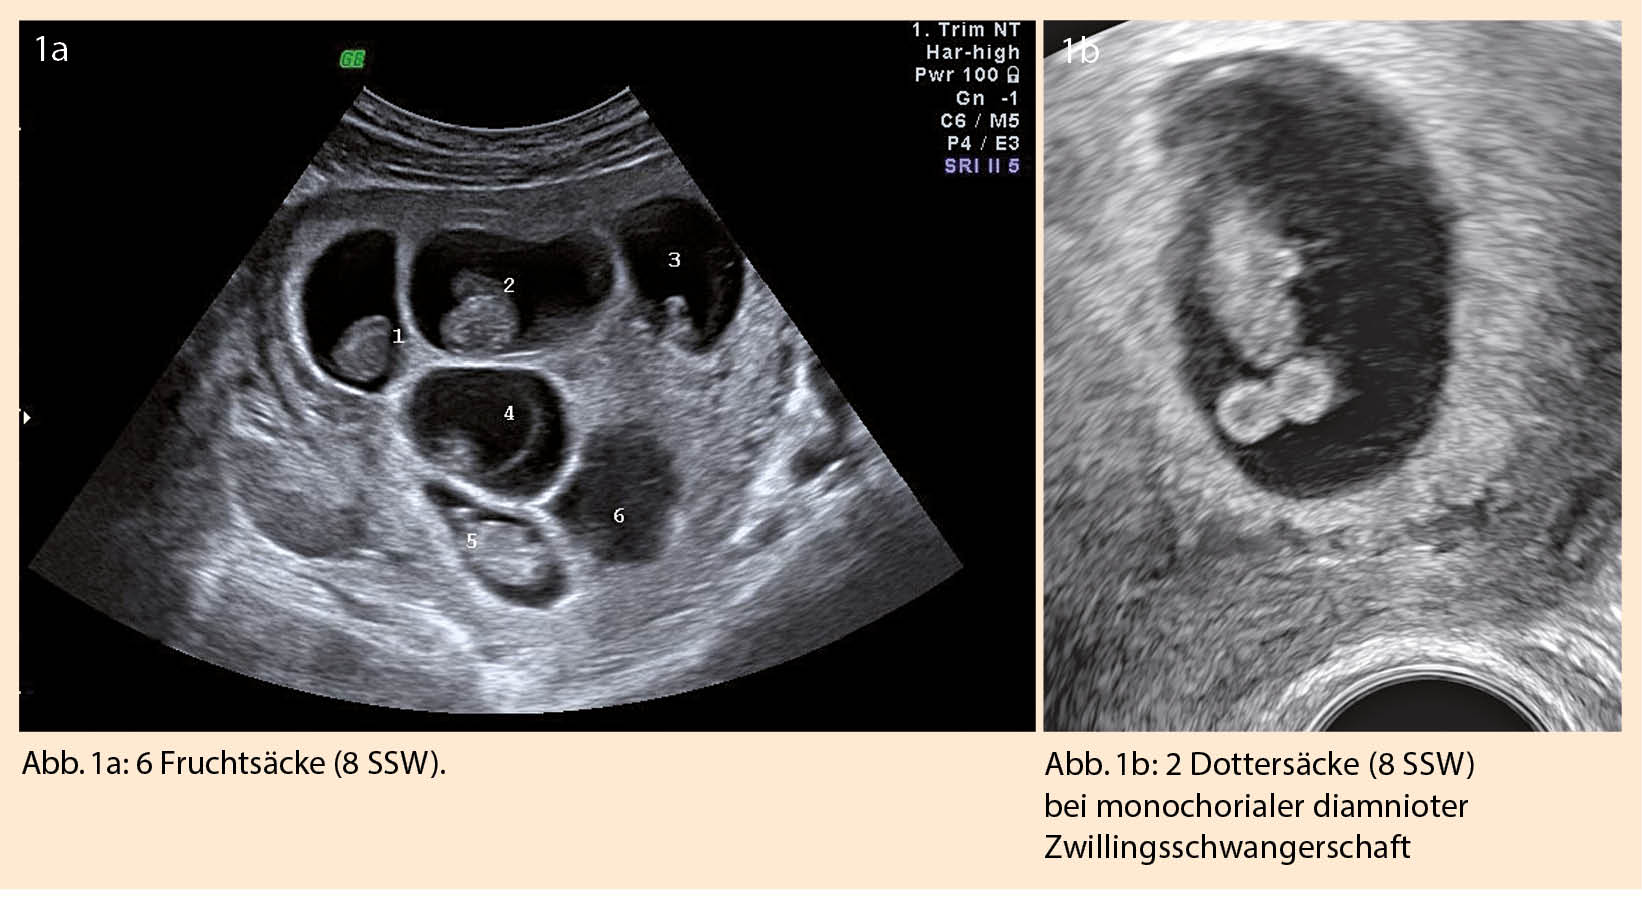

Die Anzahl der Feten lässt sich sonographisch ab der 7. SSW darstellen, indem die Fruchtsäcke gezählt werden (Abb.  1a). Ist mehr als 1 Dottersack zu sehen, muss immer an eine Mehrlingsschwangerschaft gedacht werden (Abb. 1b).

Wird eine höhergradige Mehrlingsschwangerschaft diagnostiziert, gelten dieselben Regeln zur Bestimmung der Chorionizität/Amnionizität wie bei Zwillingsschwangerschaften (Abb. 1a). Da diese Schwangerschaften mit noch höheren Komplikationsraten und grosser psychosozialen Belastungen einhergehen können, kann sich die Frage nach einer fetalen Reduktion stellen. Die Reduktion einer Drillingsschwangerschaft auf Zwillinge, kann zu einer Schwangerschaftsverlängerung von ca. 3 Wochen führen (12), geht gleichzeitig aber mit einer Abortrate von 5-7% einher (13, 14). Es empfiehlt sich vorgängig ein umfassendes Aneuploidie-Screening durchzuführen. Die Entscheidungsfindung des Paares kann selbstverständlich sehr unterschiedlich sein und hängt vom sozialen Hintergrund und deren Glaubenseinstellungen ab (15).